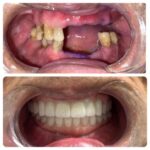

If you are searching for exceptional cosmetic dentists in a state-of-the-art dental practice in Roseville, California. You have found the right place. We also service the greater Sacramento area. As cosmetic dentists, Dr. Kwan and Dr. Hsu will provide you with a beautiful and functional smile that you’ve always dreamed of. At Nu Smile Roseville Dental, we pride ourselves on providing all guests with the most advanced cosmetic dentistry techniques and procedures, performed with the most cutting-edge technology, in a comfortable, relaxed setting.

Root canals, fillings, and other dental procedures can seem daunting, but not with Ronald L. Rasmussen DDS at your service. As a dentist in Sacramento, CA, and the surrounding areas, he offers reliable oral health solutions to clients of all ages. No matter the scope of your dental treatment, you will receive nothing less than exceptional care from the staff at this practice. Ronald L. Rasmussen DDS is a member of the American Dental Association and California Dental Association. His cosmetic solutions include dental implants and veneers, and his remedial treatments offer relief from toothaches and oral hygiene issues. He and his team are committed to providing patients with comprehensive dentistry solutions, from teeth whitening to dentures.